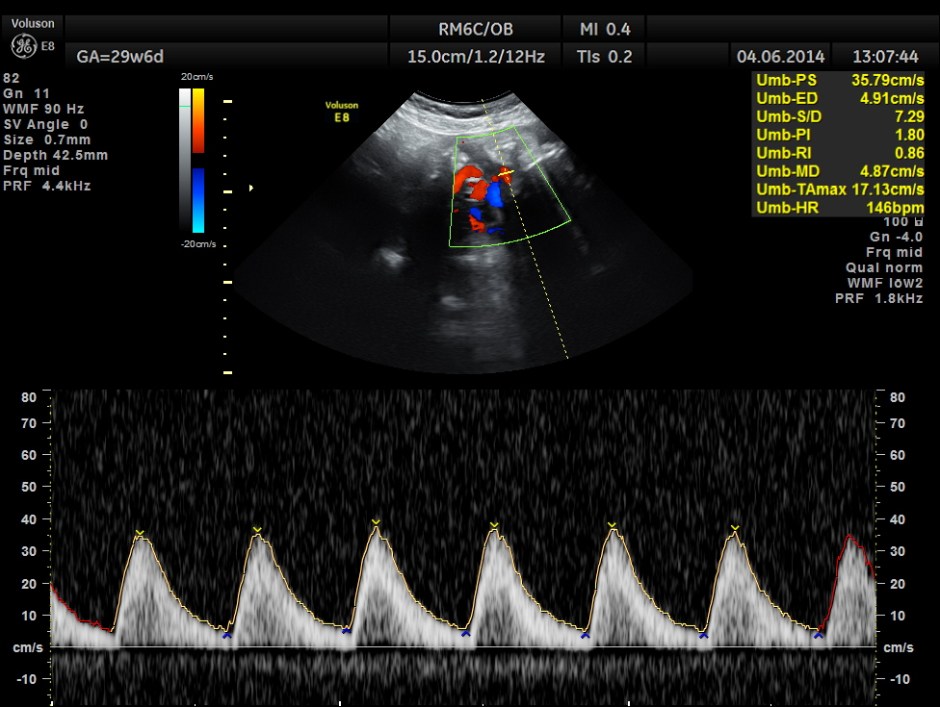

Umbilical artery P.I and R.I are high . The MCA / UMBILICAL arterial ratio is abnormal.

But the doppler values are abnormal. Umbilical artery P.I. and R.I are > 95 % tile . MCA P.I. and R.I are lower .

The cerebroplacental ratio ( MCA/UA ratio ) is abnormally low -0.70 suggestive of utero placental insufficiency.